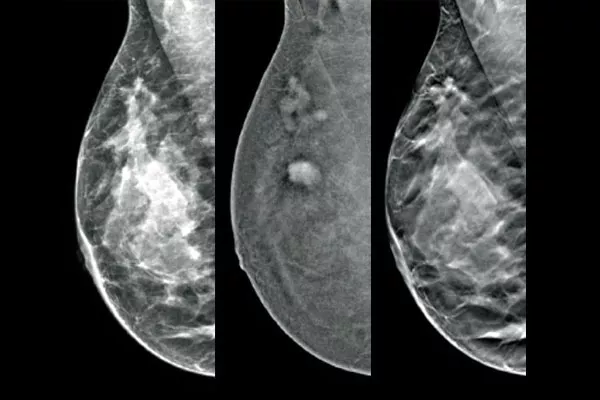

Localice y realice biopsias en lesiones identificadas mediante mamografía 2D con contraste por medio un procedimiento basado en estereotaxia, con un rendimiento diagnóstico equiparable al procedimiento de RM de mama1,2. Compare las imágenes trás la colocación del marcador en la misma modalidad que el examen diagnóstico inicial con contraste.

El software Affirm para biopsia con contraste permite realizar biopsias en lesiones identificadas durante mamografías 2D con contraste I-View™. Gracias a la posibilidad de adquirir imágenes 2D con contraste y de tomosíntesis en una sola compresión,4 el sistema de estereotaxia vertical Affirm para biopsia de mama permite una rápida transición del cribado a la biopsia, de forma que se aproveche la misma cadena de imágenes de eficacia probada5 que se empleó en el sistema de mamografía para mejorar la visualización 3D™ de lesiones sospechosas.***

Una alternativa rentable y eficaz a la RM

Las imágenes funcionales obtenidas mediante CEM son superiores a la RM de mama, al ofrecer una sensibilidad similar, mayor especificidad y mayor valor predictivo positivo.7,8 Además, la CEM supone una alternativa de diagnóstico por imagen9 más rentable que la RM, ya que reduce el tiempo de procedimiento.7,10